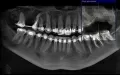

Мне 29 лет. Хочу поставить импланты на верхней левой стороне 2-ой и 3-ий зубы, на правой верхней стороне 15-ый. На нижней левой стороне 30-ый и 31-ый. На нижней правой стороне 18-ый, 19-ый, 20-ый, 21-ый.

Консультировалась с имплантологом. Мне сказали, что у меня сильная атрофия нижней челюсти и вопрос с имплантацией невозможен.

Можно ли мне сделать костную пластику с дальнейшей установкой имплантов?

При отсутствии кости можно применить бикортикальные импланты.